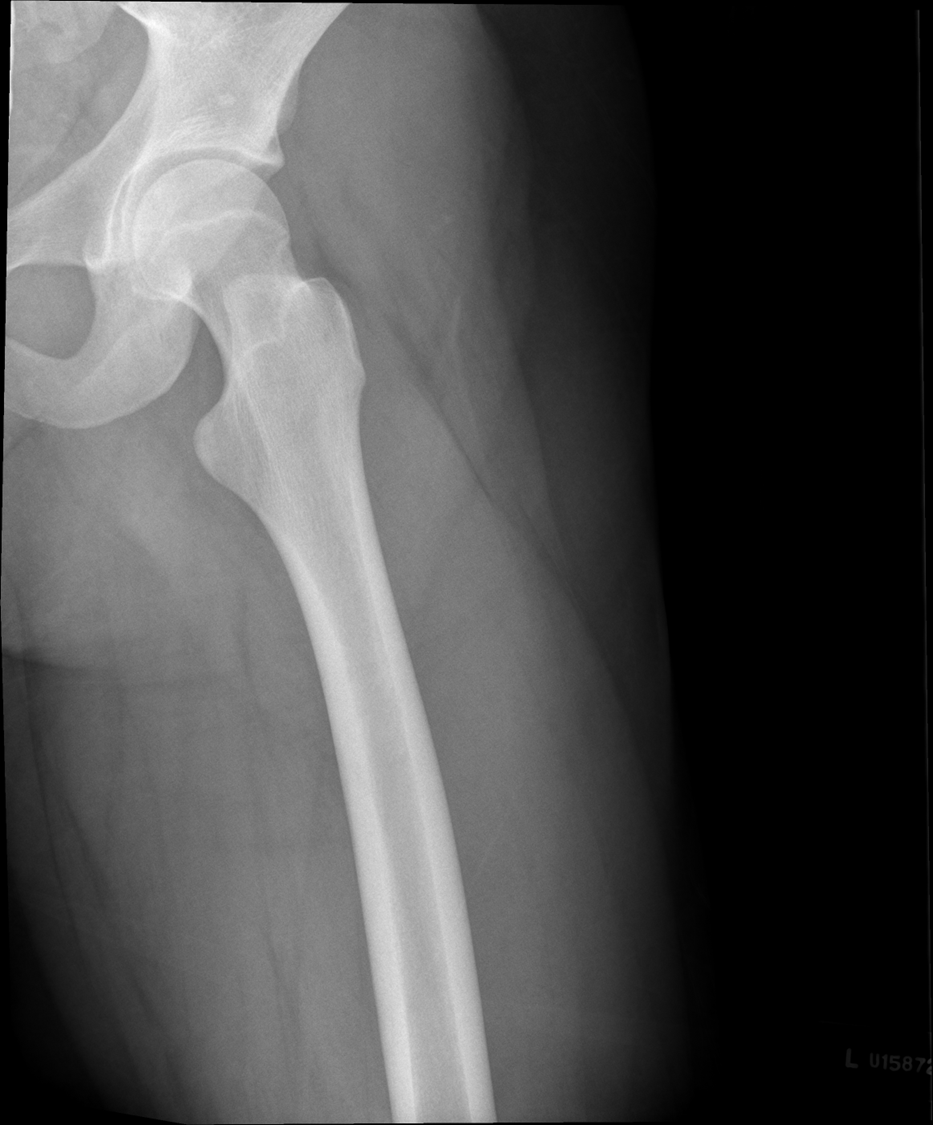

Lateral Femur

•Evidence of proper collimation and the presence of a side marker placed clear of the anatomy of interest

•Most of the femur and the joint nearest to the pathologic condition or site of injury (a second projection of the other joint is recommended)

•Any orthopedic appliance in its entirety

•Bony trabecular detail and surrounding soft tissues

With knee included (distal)

•Superimposed anterior surface of the femoral condyles

•Patella in profile

•Open patellofemoral space

•Inferior surface of the femoral condyles not superimposed because of divergent rays

Condyle is coming into patellafemoral joint space, condyle coming down and infront, ROTATION, medial condye is inferior, medial condyle is towards patella, over-rotation

fibula is popping out back

Not enough anatomy, under exposed, medial is pretty aligned, no rotation on image, increasing technique move central ray distally.